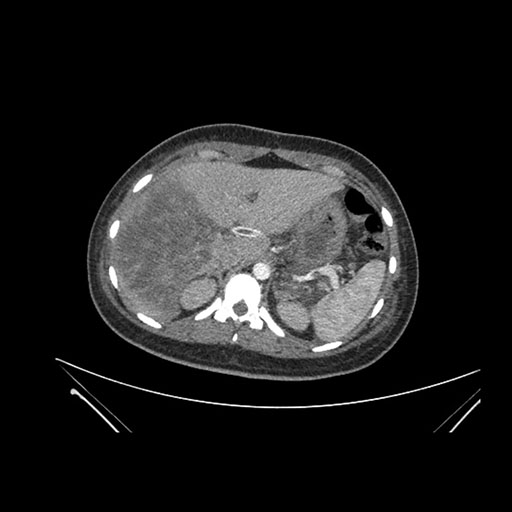

Imaging Analysis

Look through the patient's CT scan to identify any areas of concern for the necessary procedure.

Coronal Arterial

Based on initial findings, which issue(s) would you be most concerned about?